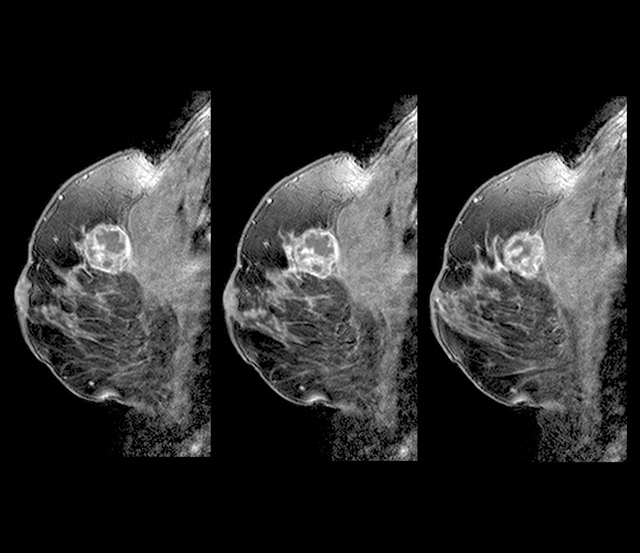

전 세계 여성 3명 중 1명이 암에 걸린다고 알려진 유방암에 좋은 음식과 유방암에 나쁜 음식에 대해서 살펴보도록 하겠습니다. 유방암은 갑상선암에 이어 여성에게 두 번째로 흔한 암이며, 중년 여성의 암 사망률 1위입니다.

유방암은 유방에서 발생하는 모든 악성 종양의 그룹이라고 합니다. 유방암은 유방의 비정상적인 조직이 계속 자라거나 다른 장기로 퍼지는 위험한 질병이라고 합니다. 가장 두드러진 원인은 DNA 손상 및 유전자 돌연변이와 같은 유전적 조건입니다.